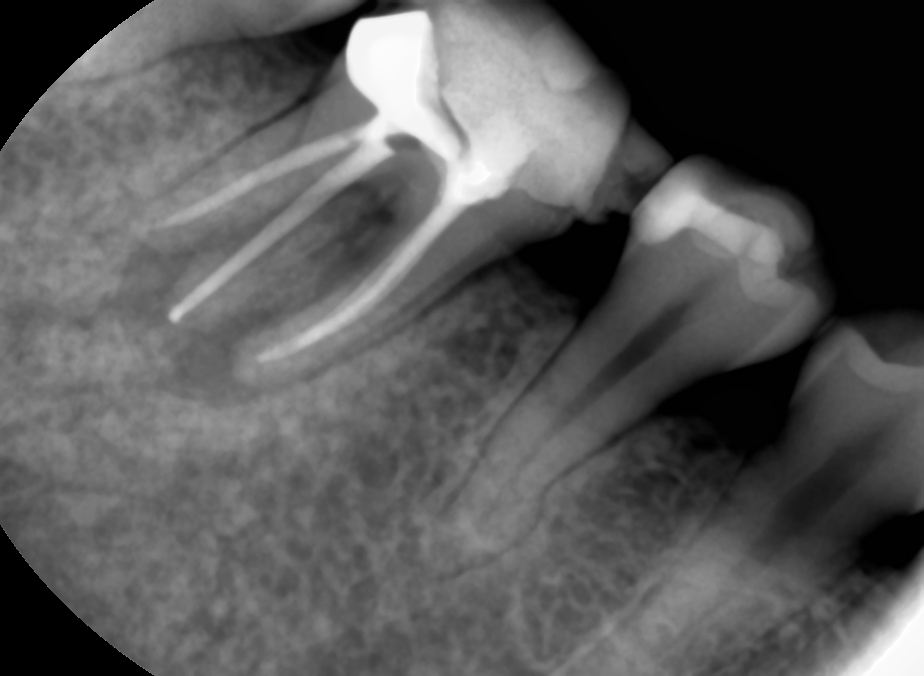

case 4. 잇몸에 뭐가 났어요